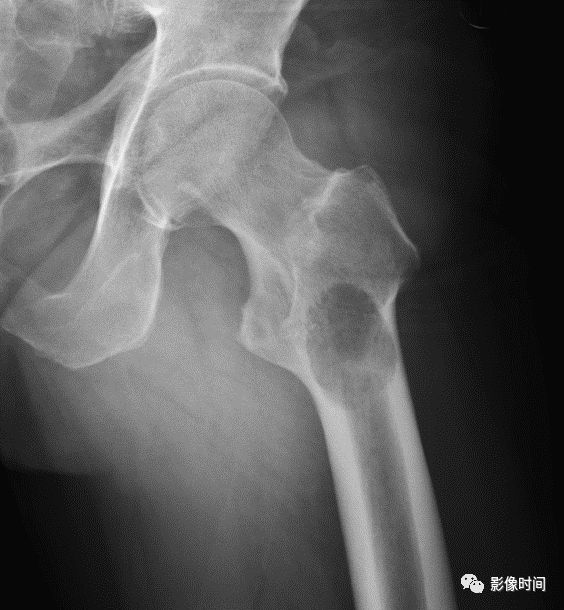

(一)地图样破坏  地图样破坏是指肿瘤组织在一个局部呈团块状生长造成界限清楚的骨质破坏(图 1、图 2、图 3、图 4)。

病灶可位于骨的中心或一侧部位,呈圆形、卵圆形密度减低区,与正常骨质分界清晰,边缘可有或无硬化带围绕,骨的形态无变化,病灶内可完全透亮或可见粗细不均、大小不等的残留骨嵴,内缘可光滑或呈分叶状压迹。

地图样破坏见于大多数良性肿瘤和肿瘤样病变如单纯性骨囊肿、骨纤维结构不良、血管瘤等、也可见于部分恶性骨肿瘤如骨转移瘤、骨髓瘤等。

图 1  地图样破坏:单纯性骨囊肿

图 2  地图样破坏:骨纤维结构不良

图 3  地图样破坏:骨内脂肪瘤

图 4 地图样破坏:骨转移瘤